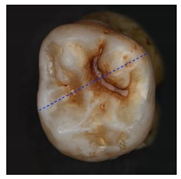

Table 3.

Clinical simulation of enamel health predictions using HSI-based automated classification as a decision-support system. Five additional teeth (two stained [(a) and (b)], three stained lesion [(c) through (e)]) were imaged and classified by the previously trained fine kNN classification algorithm (i.e., the samples in this table were not included in algorithm training). Stained sound enamel is displayed green, whereas lesions (stained or unstained) are displayed red. Polarization microscopy images from each tooth’s sectional plane (dotted lines) serve as reference. All scale bars = 1 mm.